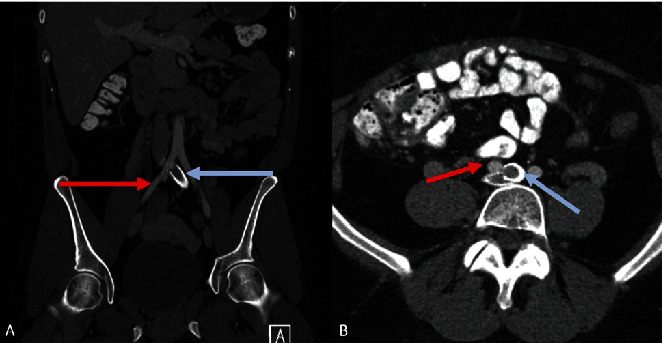

This case report describes an instance of vulvar lymphangioma occurring in the setting of May-Thurner syndrome (MTS), an association between two vascular conditions that we do not believe has been previously reported. Lymphangioma, also known as lymphatic malformation, is a benign lesion typified by dilatation of endothelial-lined lymphatic channels involving the skin and subcutis, which can occur either as a congenital abnormality or as a result of acquired damage to lymphatic channels. Lymphangioma is a rare lesion in the vulva. MTS, also known as iliac vein compression syndrome or Cockett's syndrome, is a condition of left iliac vein obstruction due to overriding the right common iliac artery which can lead to iliofemoral deep vein thrombosis. In this report, we describe the case of a 29-year-old woman with MTS diagnosed at 7 years of age with poor lymphatic drainage and pelvic pain requiring left iliac vein stenting. She presented with left vulvar discomfort and chronic lower extremity edema and was found to have warty vulvar masses, with histopathological examination showing lymphangioma of the vulva. We believe that this is the first report of vulvar lymphangioma recognized in the setting of MTS, and we will discuss the clinical features, etiology, and possible pathophysiologic association between these two entities.